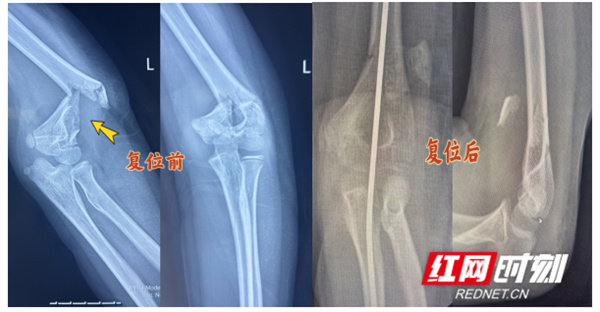

红网时刻新闻3月17日讯(通讯员 李承学)近日,永州市中医医院正骨中心迎来暖心一幕:10岁患儿小宇(化名)的家属将一面印有“医骨神技,情暖人心”的锦旗送到医生手中,言语间满是感激。此前,小宇因肱骨髁上骨折且移位严重,在外院被告知需开刀手术上钢板治疗,小宇的父母忧心不已,四处打听后,慕名来到永州市中医医院寻求保守治疗方案。永州市中医医院正骨中心团队凭借精湛的医术成功为患者实施手法复位,让孩子免受手术之苦。

经过一段时间的规范治疗与精心护理,小宇复查时显示骨折端对位良好,骨痂生长顺利,肘部肿胀、疼痛完全消失,肢体活动功能逐步恢复。“原本以为孩子要挨一刀,没想到在你们这儿不用手术就治好了,孩子少遭罪,我们也放心,真的太感谢你们了!”小宇的父亲激动地说道,特意定制锦旗送到科室。

一面锦旗,不仅是家属的感激,更是对医院医疗技术与服务的肯定。肱骨髁上骨折是儿童常见肘部骨折,移位严重时治疗难度较大,保守治疗对医生的手法复位技术、复位后固定及康复指导要求极高。